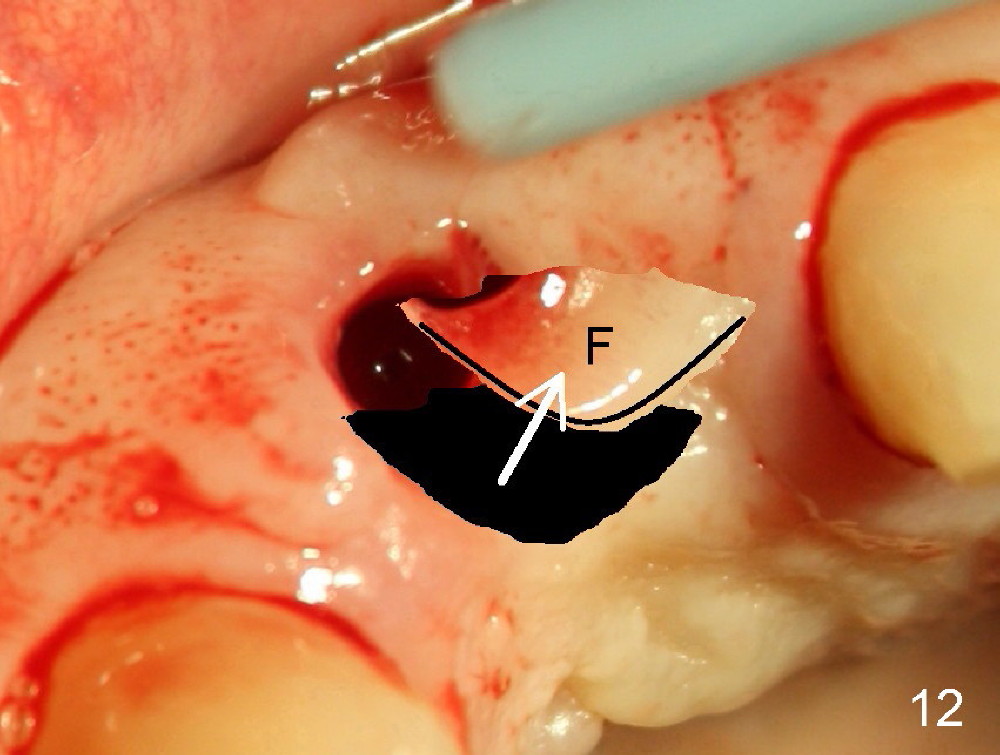

Malpositioned implant in the anterior region is cosmetically unacceptable. Immediate provisional allows us to note the issue immediately. The crown looks too long. Secondly, the provisional is easily dislodged, since the buccal aspect of the angled abutment is over trimmed (Fig.1). The implant (3.8x14 mm), which has been placed 3.5 months, is unexpectedly easily removed by reverse torque (Fig.2). The buccal wall is intact, whereas there seems to be enough bone lingually to place an implant. A small incision is made (Fig.11) so that the gingival tissue can be transferred buccally (Fig.12) and the immediate implant is to be placed palatally (Fig.13 white circle). There is no difficulty forming osteotomy in the palatal wall, followed by inserting 4.5x20 mm tap at the depth of 17 mm (Fig.3,5). But the tap is not palatal enough (Fig.4). By removing more palatal bone, the 4.5x17 implant (Fig.6) appears to be placed palatally enough for restoration (Fig.7; A: abutment; *: buccal gap). The biggest problem is that the palatal flap (Fig.7 arrowheads) cannot be pushed buccally; instead remains palatally. This leads to buccal tissue deficiency (Fig.8). Connective tissue graft is offered, but declined. The patient insists that she has low smile line. Following immediate provisional, mixture of allograft and synthetic graft is placed in the buccal gap (Fig.9). The overbuilt graft is held in place by perio dressing.

If a larger incision were made (Fig.14) and the flap were dissected freely (Fig.15), the buccal tissue deficiency would be less (Fig.16). Follow up is shown 2 3.